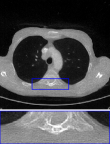

CT We evaluate on computed tomography with Gaussian noise, modeled as , where is the Radon transform. The acquisition uses 51 angles, i.e., about of the LIDC-IDRI image width, with as in training. Results are reported in the rightmost column of Table 2 and visuals in Figure 8. DPIR results are omitted due to instability on this task. The proposed RAM model produces reconstructions with finer details than uDPIR-tied.

CT

We provide in Figure 8 visual results for computed tomography for the in-distribution setup on the top row (i.e., with a setup similar to that of training), and the out-of-distribution setup on the bottom row. In the latter case, measurements are degraded with additional Poisson noise, unlike the training setup.

| uDPIR tied | RAM | Ground-truth | ||

| Gaussian CT | ![]() |

![]() |

| 0.607 | 0.642 | SSIM | ||

| Poisson CT | ![]() |

| 0.828 | 0.671 | SSIM |